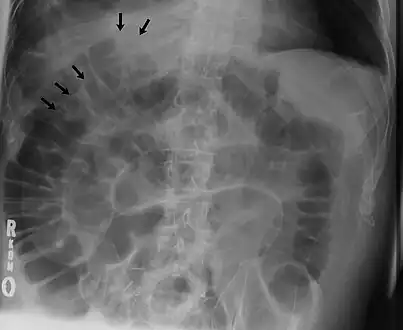

Signs that can be seen on projectional radiography are shown below:

The double wall sign marks the presence of air on both sides of the intestine.[27] However, a false double wall sign can result from two loops of bowel being in contact with one another.[28] The sign is named after Leo George Rigler.[29] It is not the same as Rigler's triad.